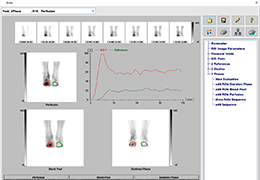

Performs 3D reconstruction and volume rendering.

Multi-planar slicing.

Oblique slicing.

Window/level (brightness and contrast) presets.

Side-by-side comparative assessment for pre- and post-operative scans.